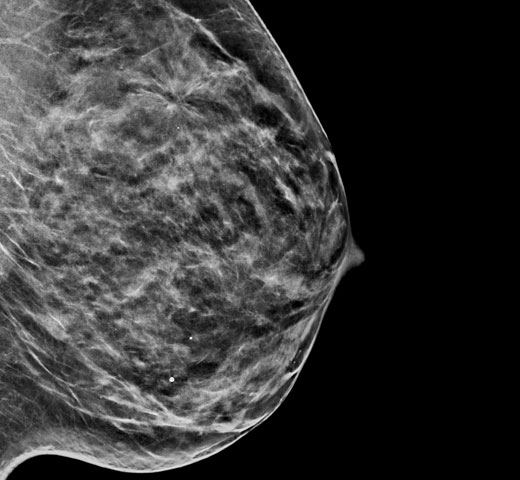

Kontrastforbedret mammografi (CEM) – billeddannelse af et bryst ved hjælp af jodholdig kontrast for at afsløre områder med øget blodforsyning i brystet – kan bidrage til at fremhæve mistænkelige læsioner. I-View-softwaren kan kombinere styrken i CEM med 2D- og tomosyntesebilleder, alt sammen under én kompression, hvilket giver anatomisk og funktionel billeddannelse i én undersøgelse.1

Denne software registrerer både anatomiske og funktionelle oplysninger i en enkelt undersøgelse ved at udnytte vores evne til at levere 2D-, kontrast- og tomosyntesebilleder i blot én kompression.1